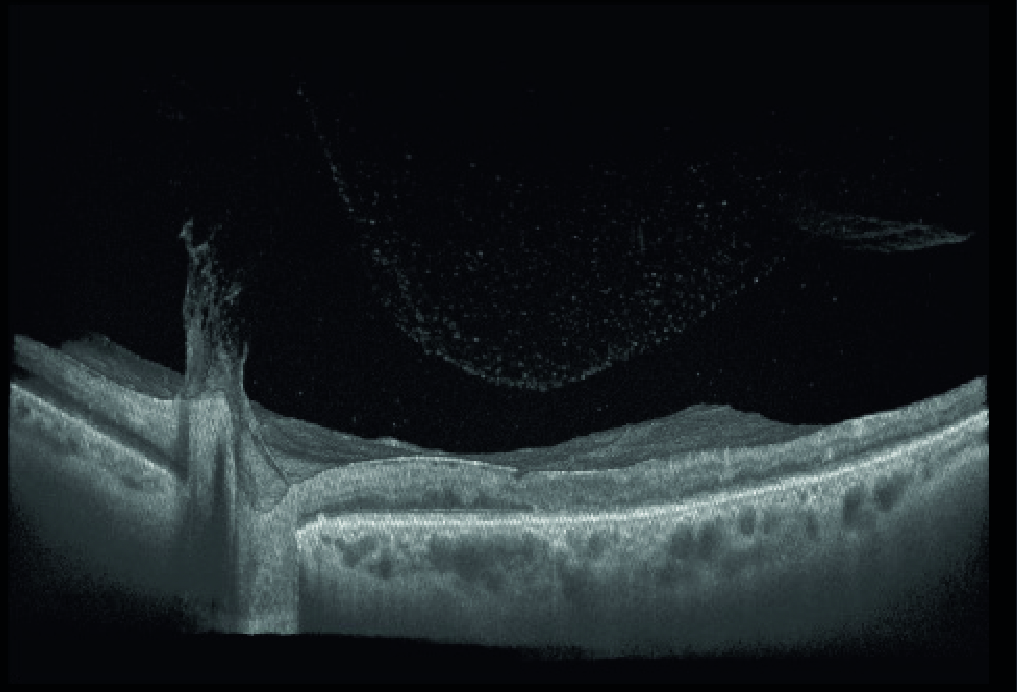

Помутнение стекловидного тела, витреодисковая тракция, эпиретинальная гиперрефлексия в макулярной области и интраретинальный отек | Пролиферативная диабетическая ретинопатия